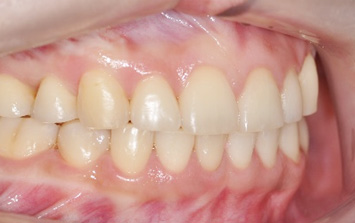

앞니가 정상적으로 물이지 않아 심미적인 문제와 음식물을 섭취할 때 상당한 불편함을 느껴 내원한 환자.

고운미소에서는 교정용 와이어와 미니스크류를 사용하여 치열의 수직적인 문제를 개선하는 치아교정을 시행하였습니다.

앞니가 서로 물리게 되어 음식물을 씹는 저작 문제와 심미적인 문제가 해결되어 교정을 완료하였습니다.